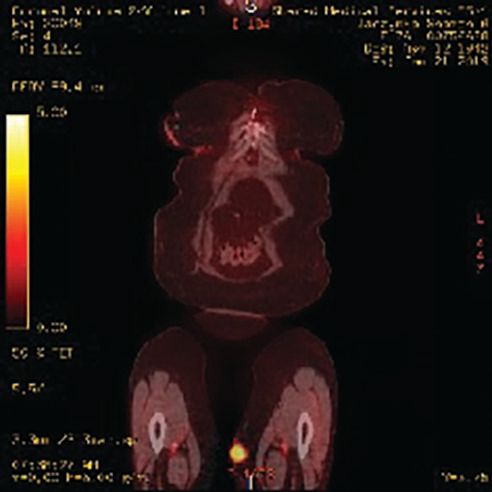

A woman, aged 76 years, presented with a bluish-purple lump in her mid- to upper medial left thigh. It started initially as a flat rash, and over a 2-month period, it turned into a mass measuring 2.5 cm by 3.1 cm (Figure 1). Work-up, including a PET-CT scan, showed the soft tissue mass on the inner thigh to have a Standardized Uptake Value of 4 (Figure 2); there were no other sites of disease. A biopsy of the lesion was performed (Figure 3).